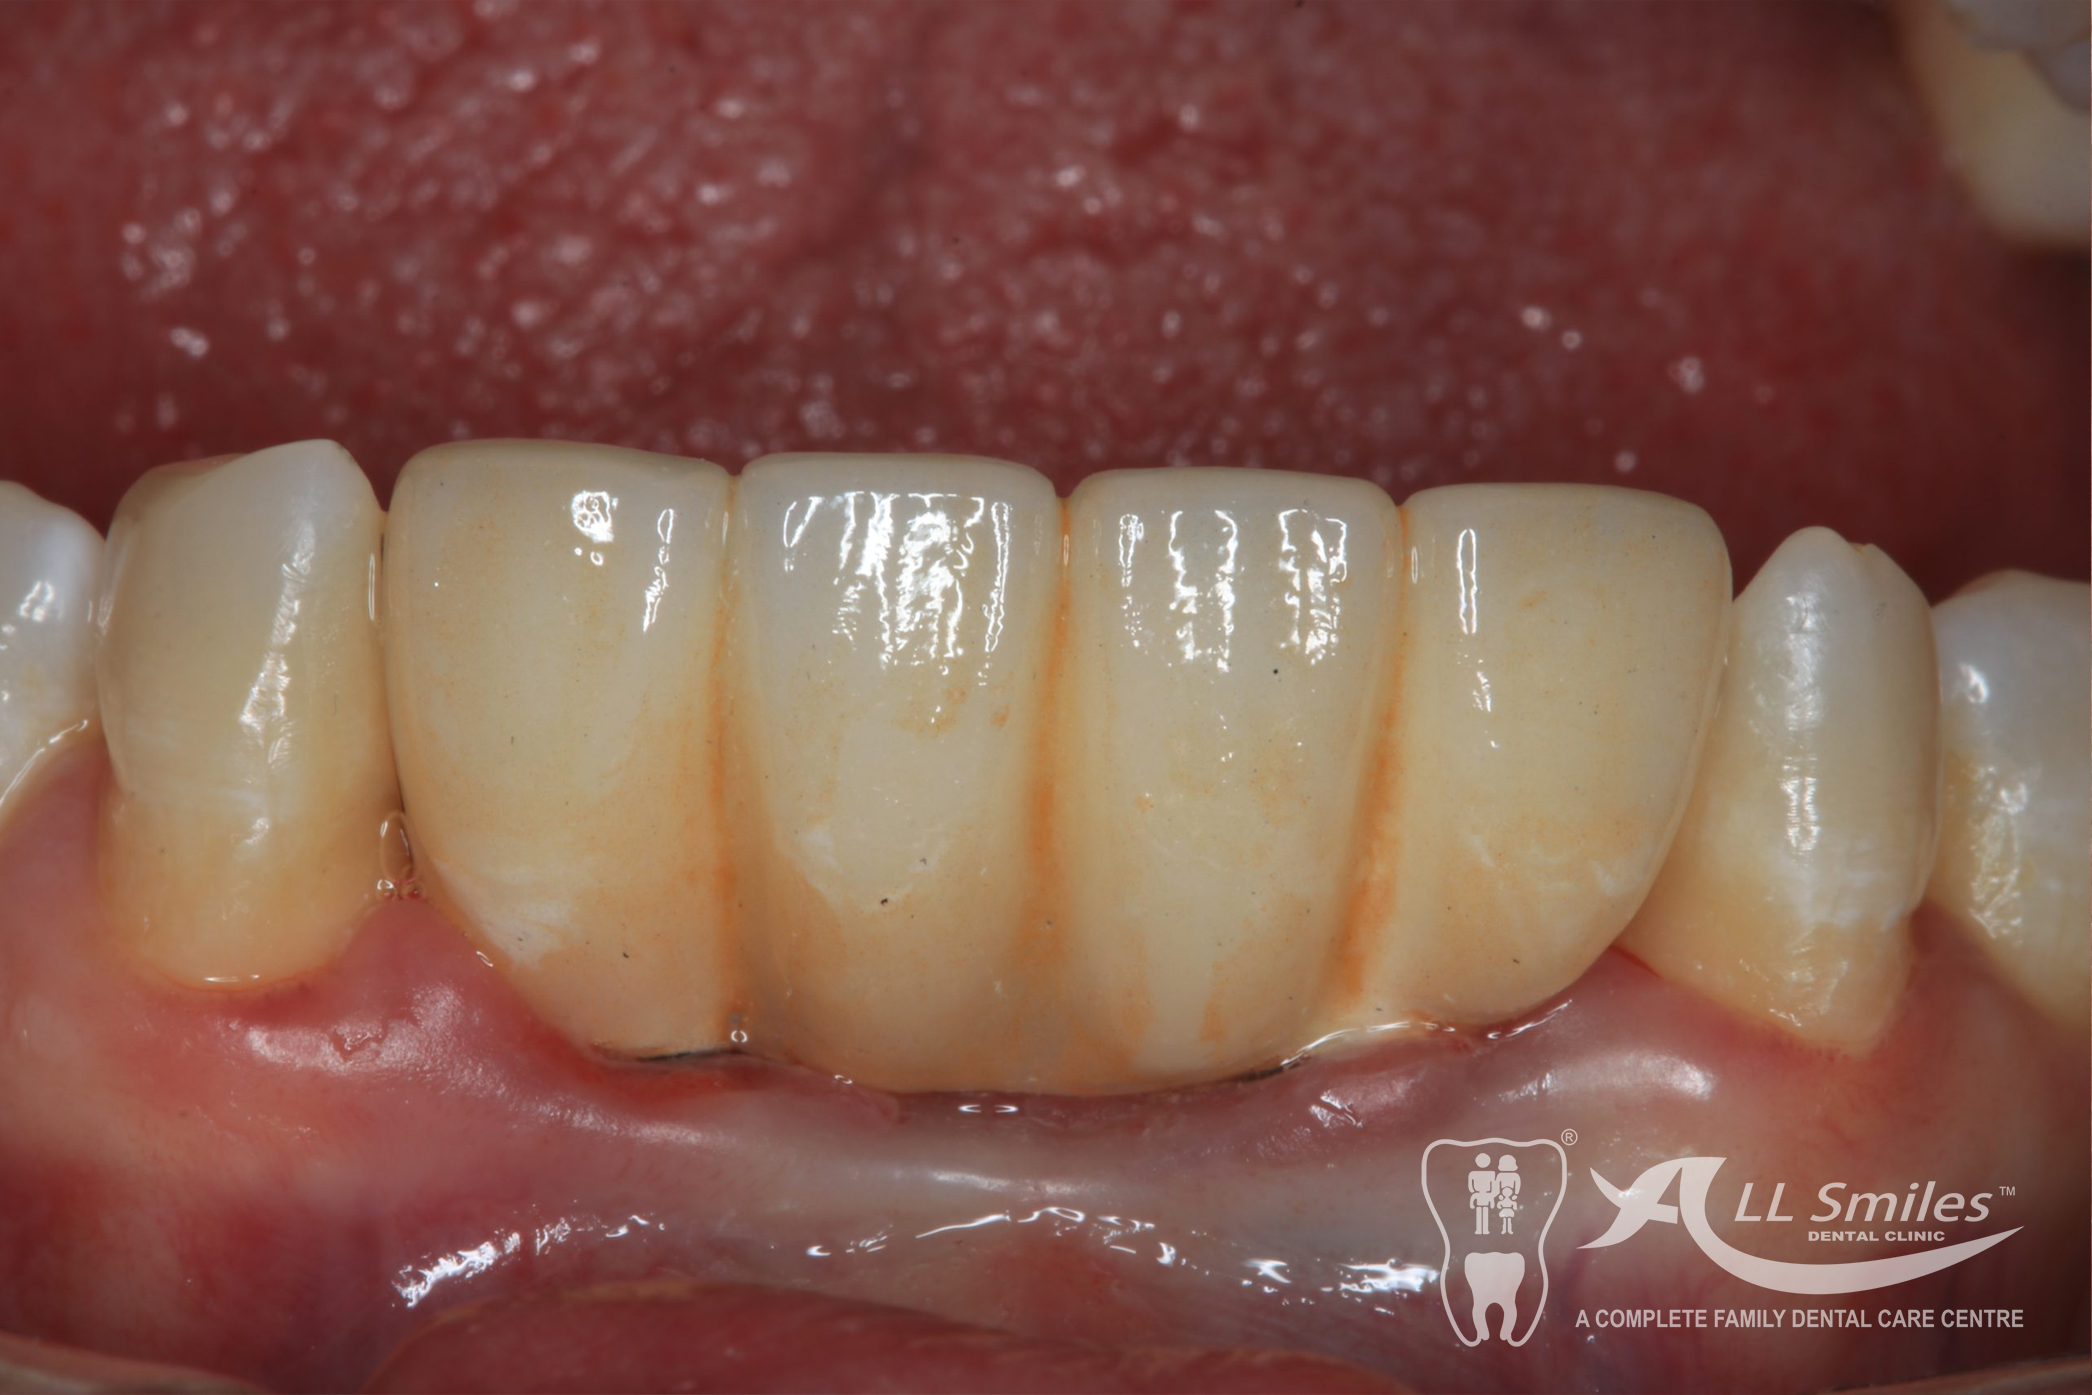

Dental Implants Gallery

Dental implants provide a stable and durable solution for missing teeth that can improve your ability to eat, speak, and smile with confidence. They also help to preserve the surrounding bone tissue and prevent further tooth loss, and they look and feel natural, similar to your natural teeth.